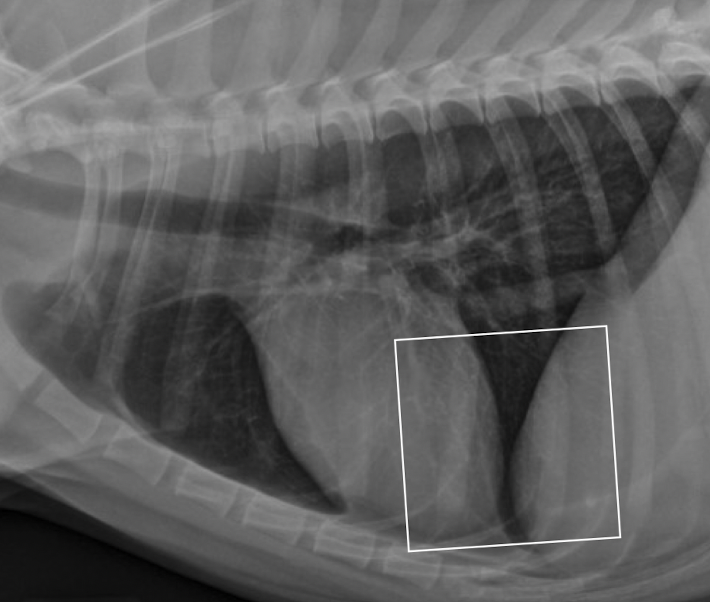

ddx

caudodorsal mediastinal mass * Caudodorsal mass, cranial convex margin * Focal widening (midline with bulge to right) **hiatal hernia** gas inside structure